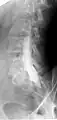

Myelography punction

Conventional myelography in oblique projection. You can see the individual nerve root sheaths.